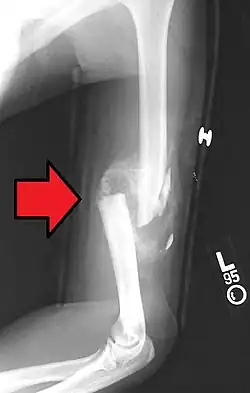

A transverse fracture of the humerus shaft -